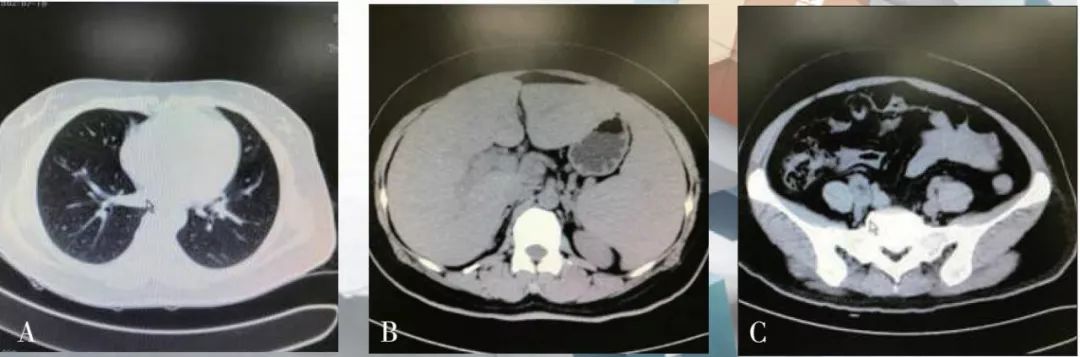

CT结果(图1)显示:双肺支气管血管束清晰,右中肺内侧段见小条片状密度增高灶,边界清,余肺内未见明显异常密度灶;气管支气管通畅,纵隔内可见数个小淋巴结,直径约5 mm,未见胸水征;肝脾形态饱满,脾脏增大,脾下缘超过肝下缘,胆囊体积不大,胆囊壁增厚,壁稍毛躁,囊内未见异常密度灶,肝内外胆管未见明显扩张;盆腔可见少量积液。

CT诊断为:① 右中肺内侧段少许炎症;② 胆囊壁水肿,可能为胆囊炎;③肝脾大;④盆腔少量积液。

图1(5月25日)患者入院后CT结果,A为胸部CT;B为腹部CT;C为盆腔CT